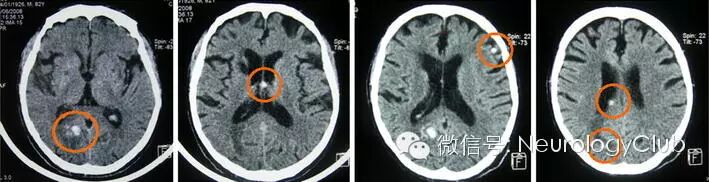

(CT提示右侧枕部,邻近右侧脑室三角区,透明隔和左侧额部多发高密度病灶